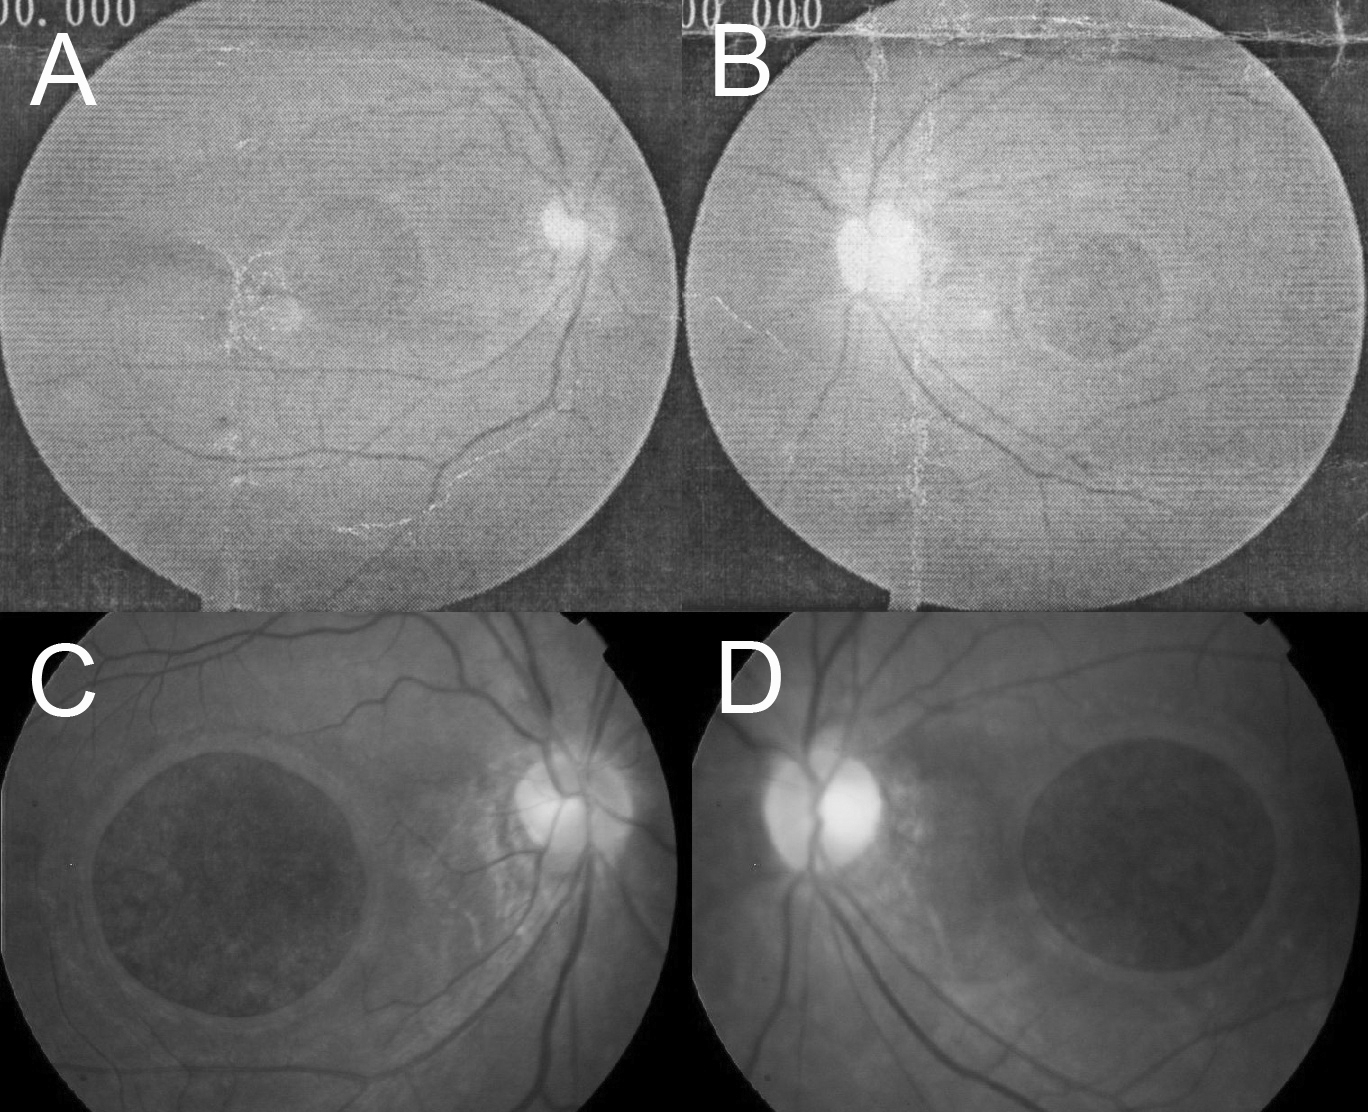

Figure 3. Slow progression of

bilateral giant macular holes. The diameters of the macular

holes were about 2 disc diameter at age 28 (A, B).

At age 33, when first referred to our hospital, the diameters of

the macular holes had increased to about 2.5 disc diameter (C,

D).